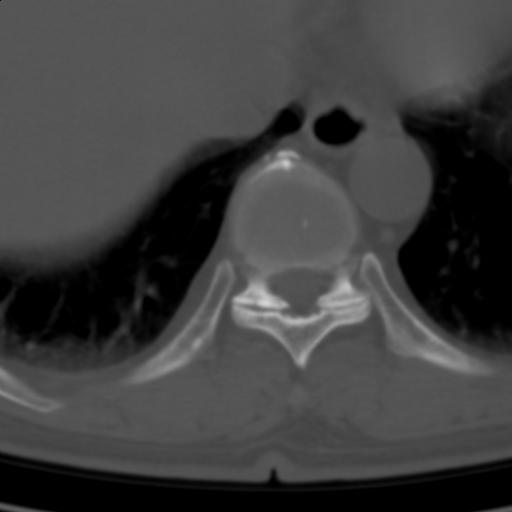

标题: CT25189:胸椎ct,请会诊!

既往食管癌,现行ct检查!

中上段食道癌,椎体轻度退变。

椎体退行性改变,食管癌。

支持中上段食道癌,椎体轻度退变,必要时做ect。